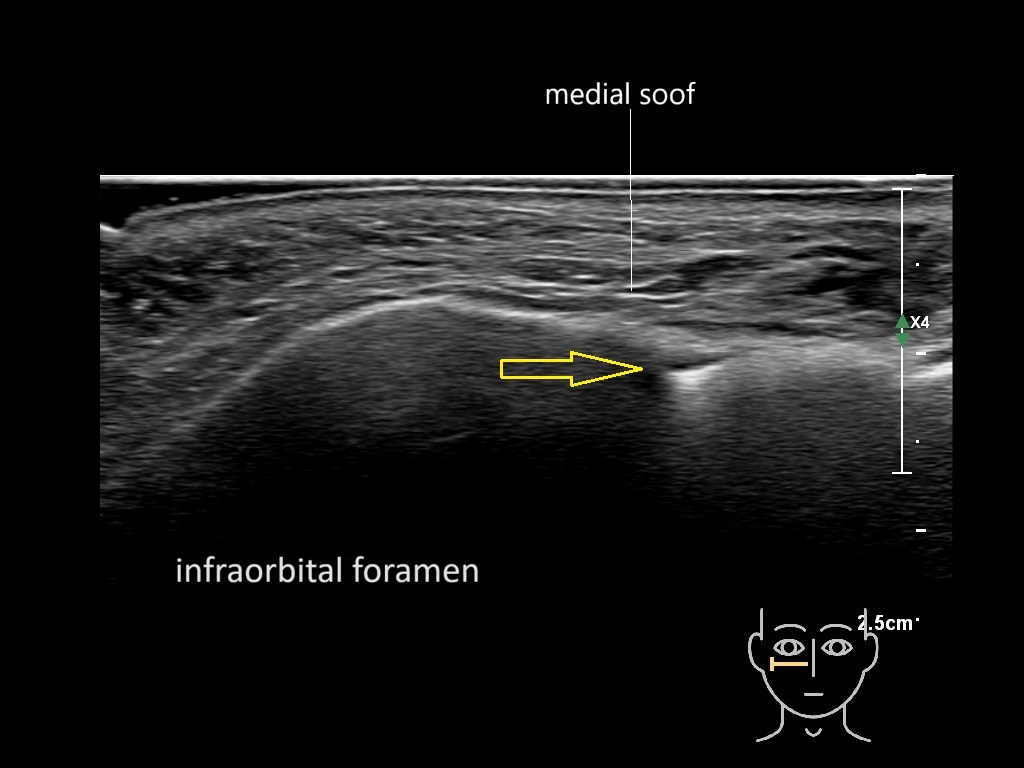

Study the first image to recognize the different layers. If you are sure about the layers, swipe to the second image to view the answer (if applicable).